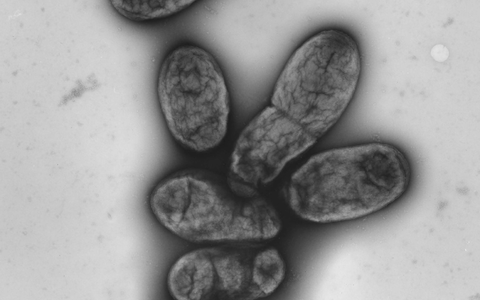

Der Pesterreger - das Bakterium Yersinia pestis - sei in vielen Teilen Kaliforniens präsent, so die Behörden. Übertragen werde der Erreger oft durch Bisse von infizierten Flöhen, die sich wiederum bei Eichhörnchen, Streifenhörnchen oder anderen wilden Nagetieren infiziert haben. Daher sei es auf Spaziergängen, Wanderungen oder beim Zelten in der Natur wichtig, Schutzmaßnahmen für Menschen und Haustiere zu ergreifen.